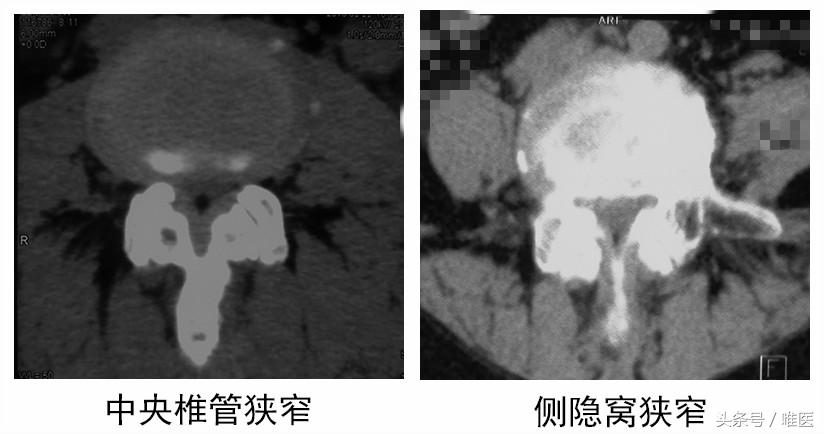

3.CT检查

CT具有较高的空间分辨力,在横截面上能够清楚地显示骨性和软组织结构,通过选用适当的窗宽,可以获得椎骨、椎间盘、黄韧带满意的层面图像,这些是X线平片和椎管造影无法比拟的。 CT扫描在诊断腰椎病是一项极好的检查手段,应用CT扫描所得结果与临床符合率高。椎管横径为双侧椎弓根的内侧缘距离,小于13mm时为绝对狭窄,矢状径为椎体后缘中央至棘突根部的距离,小于13mm为相对狭窄,小于10mm时为绝对狭窄,侧隐窝大于5mm者一般不会产生压迫症状,小于3mm约有50%的人会产生压迫症状,小于2mm为绝对狭窄。

以上测量仅限于椎管径线的测量,但人体椎管的形态并不规则,这就引入了二维的测量。Heggeness等在利用CTM对椎管横截面积进行了测量,认为正常人腰椎管横截面积为180mm2,小于100 mm2为中央型腰椎管狭窄。Ullrich等报告椎管横截面积小于145mm2为椎管狭窄。

但CT检查不足之处在于对软组织分辨率相对较低,不能直接进行矢状面、斜面扫描。对纤维环膨出显示较模糊,有假阳性情况。